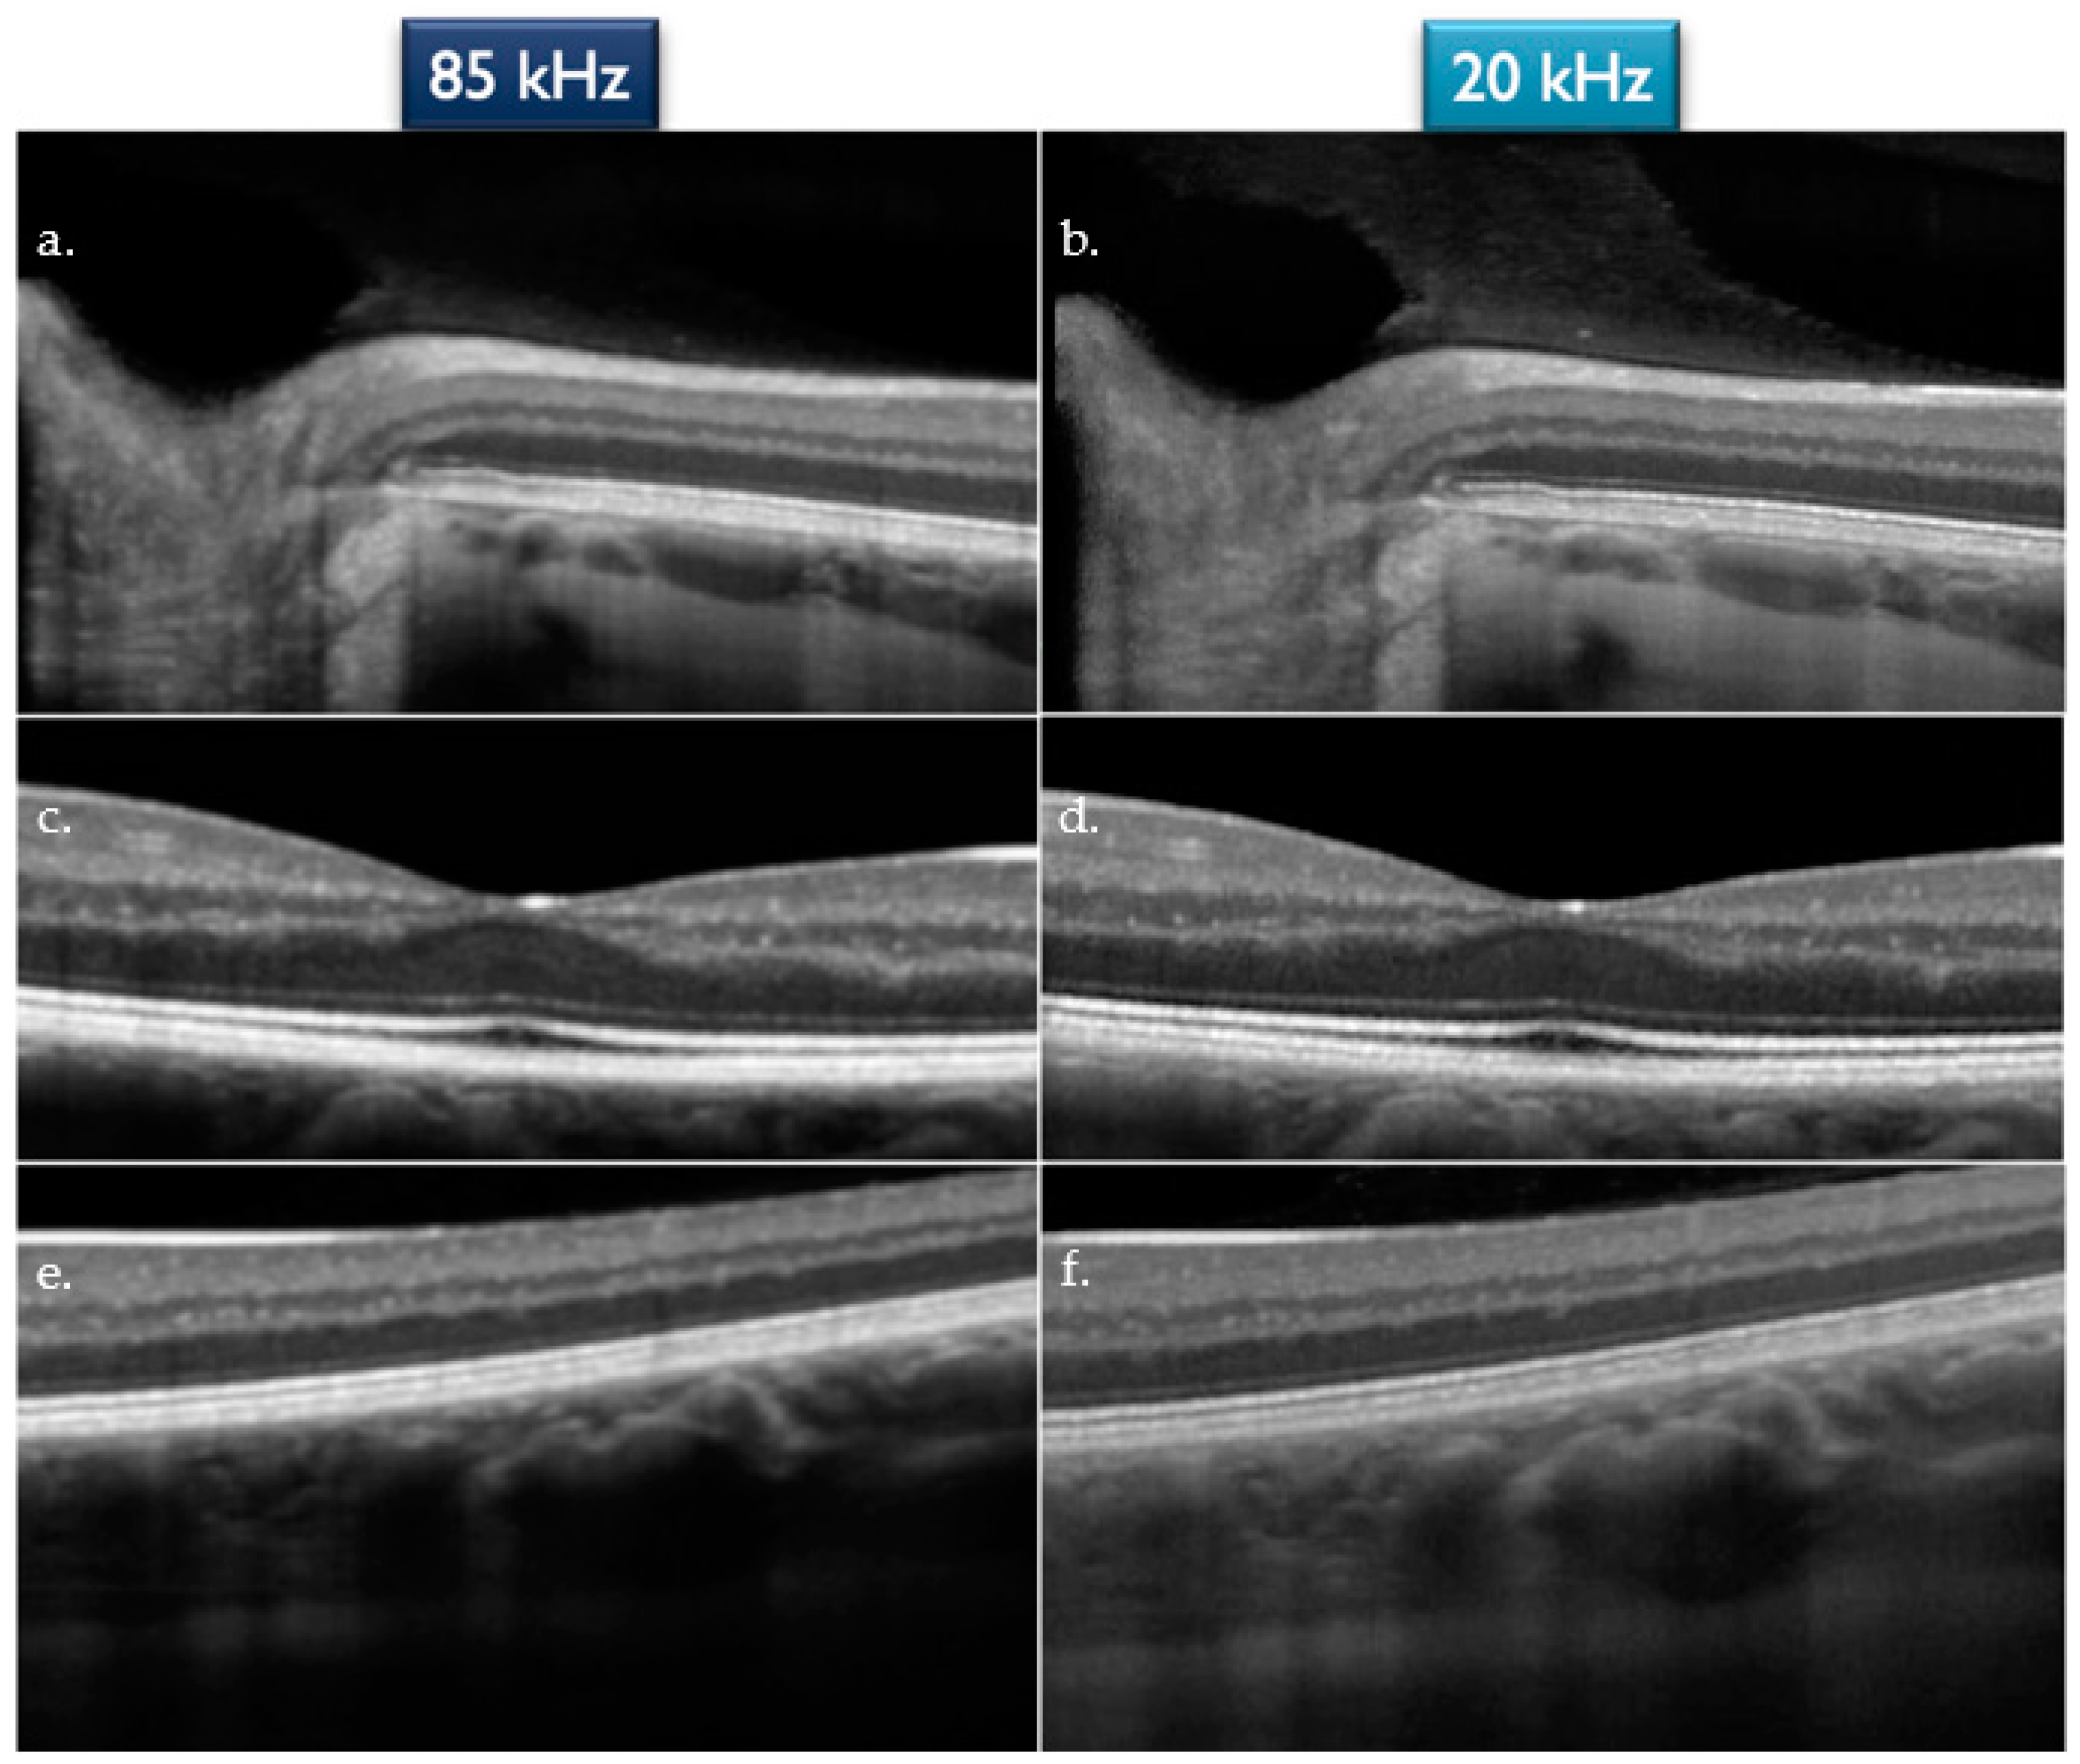

| Grade “3” | 43 (71.7%) | 38 (63.3%) |

| Grade “2” | 14 (23.3%) | 19 (31.7%) |

| Grade “1” | 3 (5%) | 3 (5%) |

| Grade “3” | 25 (41.7%) | 28 (46.7%) |

| Grade “2” | 27 (45%) | 24 (40%) |

| Grade “1” | 8 (13.3%) | 8 (13.3%) |